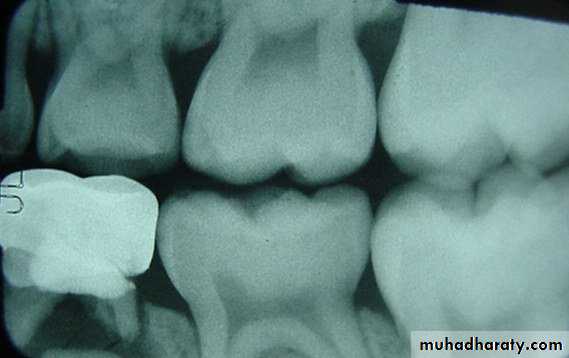

Bitewing radiograph. This radiograph shows (1) large occlusal caries, (2) radiolucent lines or mach band effect (an optical illusion caused by overlapped enamel), (3) interproximal caries, and

(4) cervical burnout